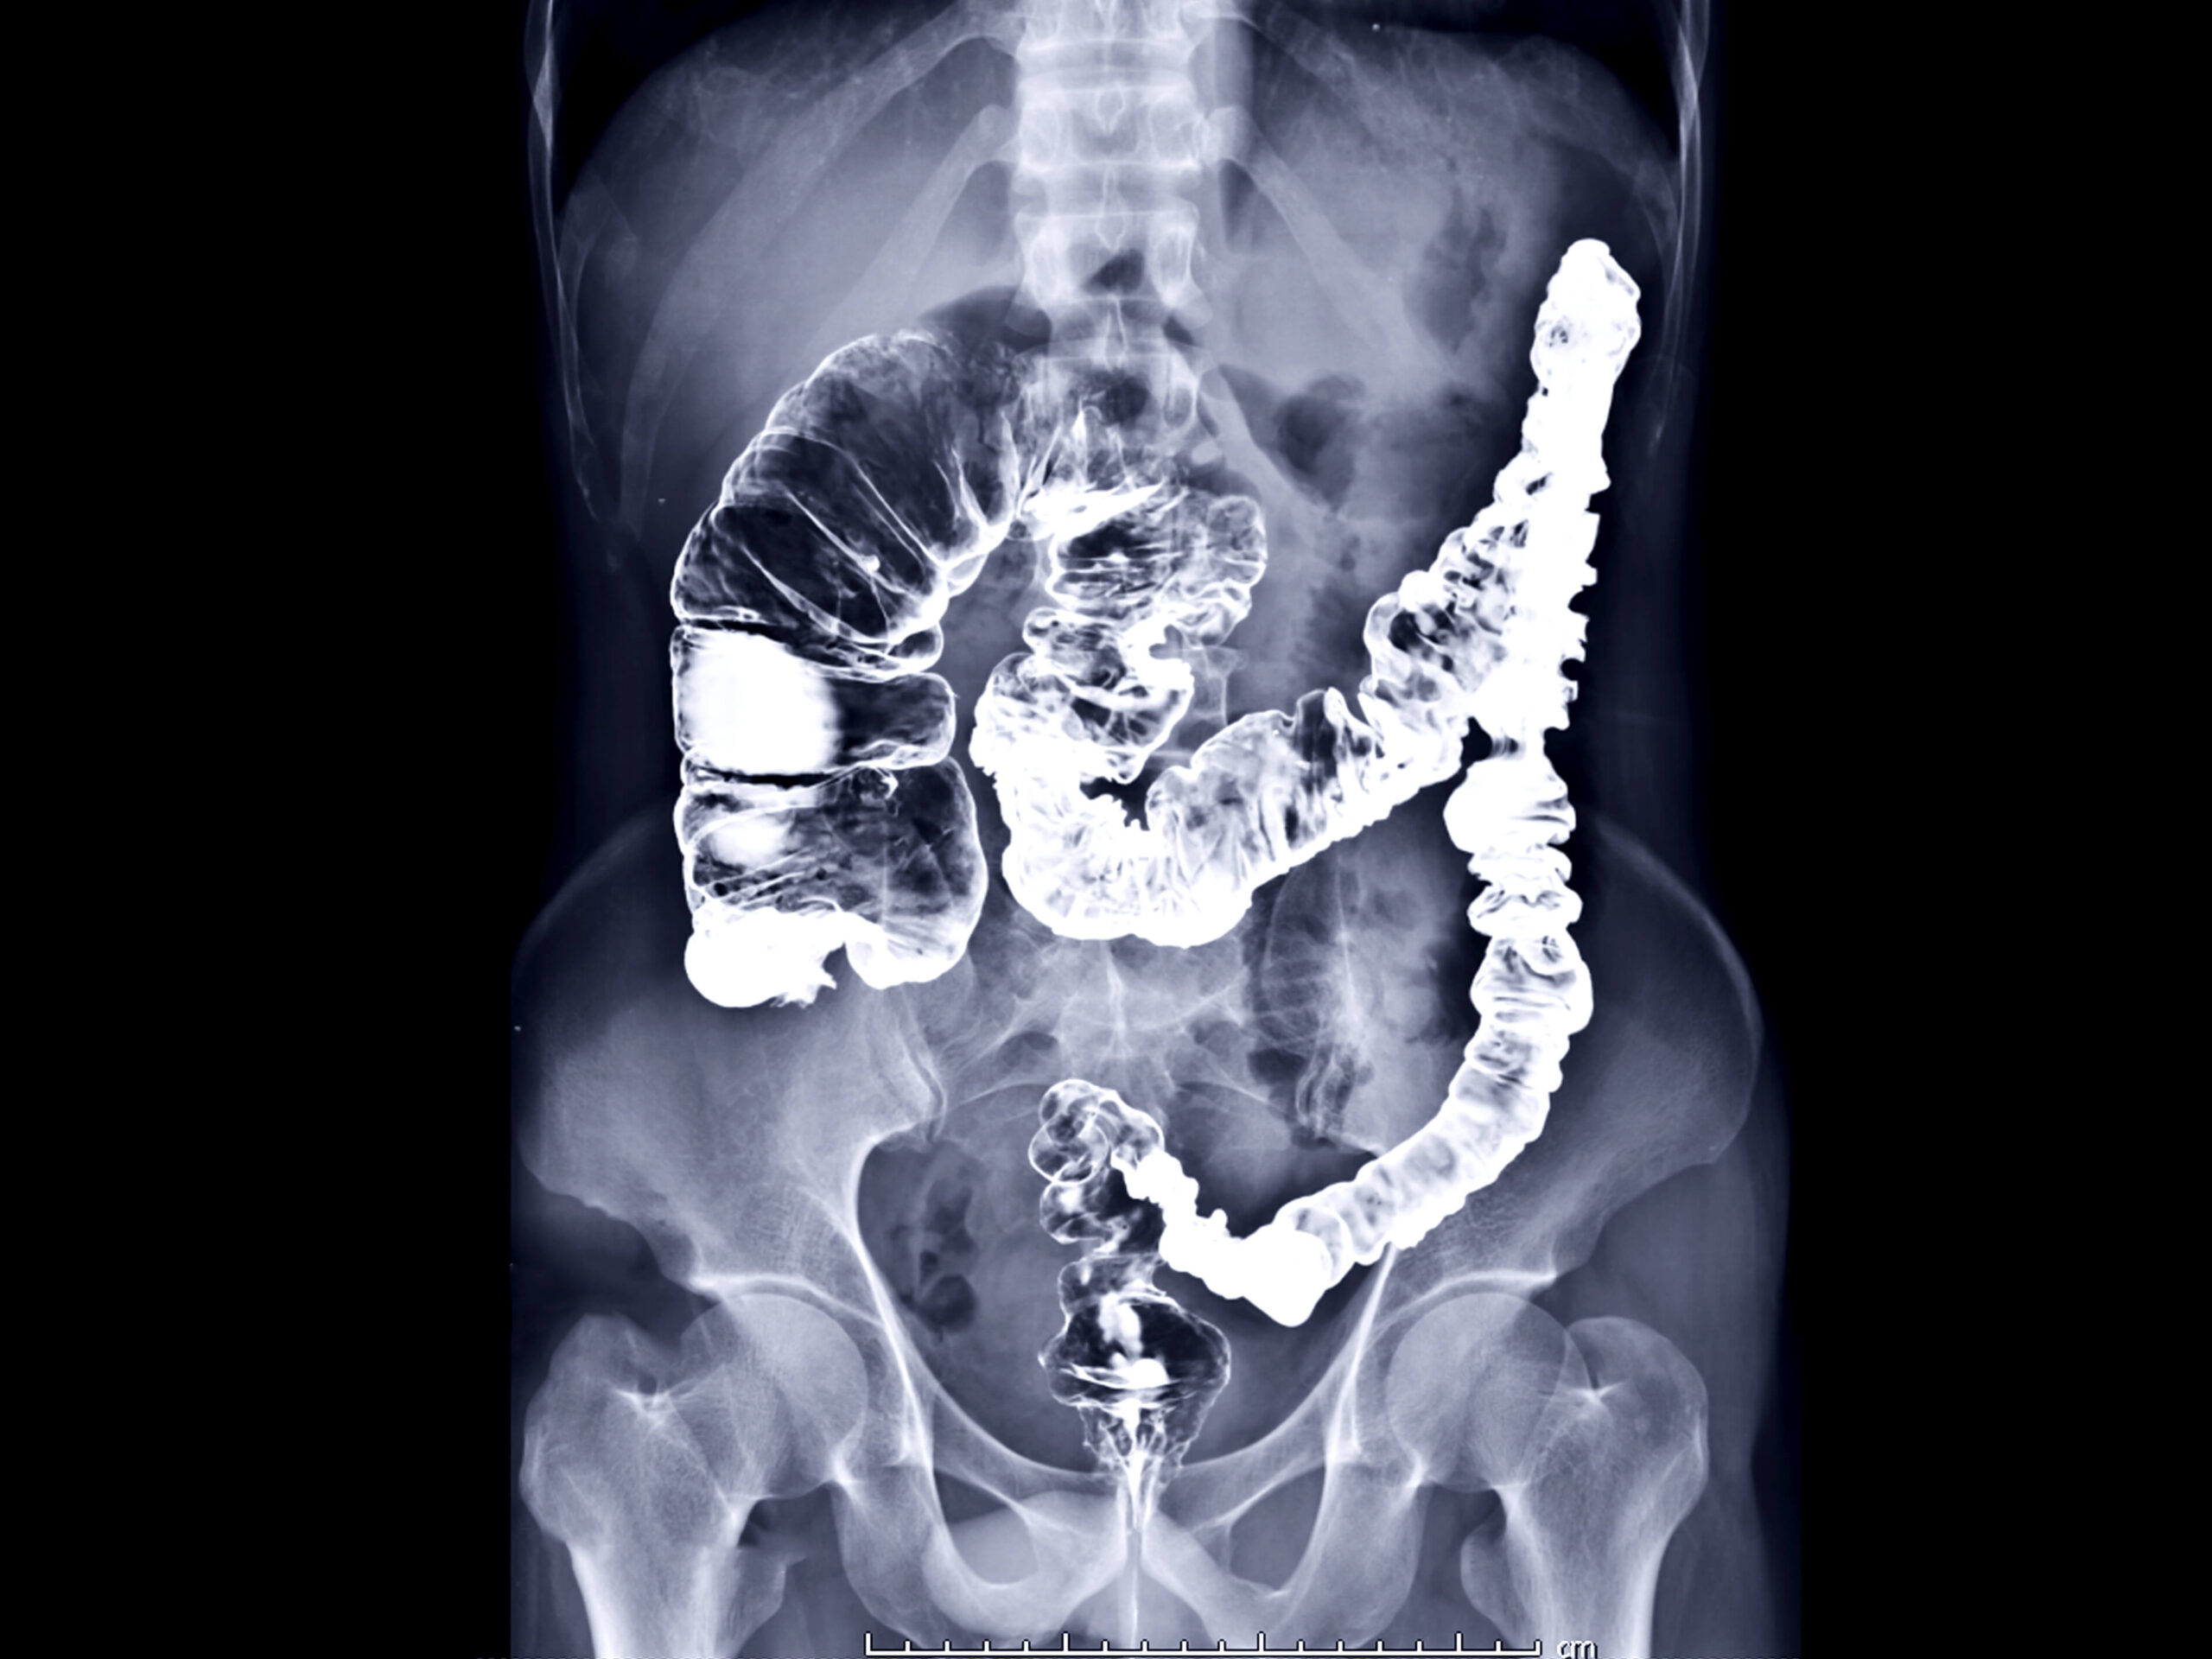

Fluoroscopy uses low level X-rays to obtain real-time moving images of your body’s internal structures. It displays the movement of a body part or dye (contrast material) through the body.

Common uses include diagnosis of gastrointestinal disorders, joint injections for orthopaedic pain and problems, and infertility examinations.

Our technologist will take a brief medical history. You will be positioned on the fluoroscopy table, either on your side or back. For gastrointestinal exams, you may be given barium (a contrast) to drink during the exam. If a barium enema is being performed, a small rubber tip will be inserted in your rectum, where barium will be allowed to flow into your intestine. There may be slight cramping. If you are undergoing an arthrogram for orthopaedic purposes, the affected joint will be cleansed and a needle inserted into the joint space, where contrast or cortisone will be released. For all procedures, a radiologist will be in the room reviewing the images in real time, and you may be asked to change positions.